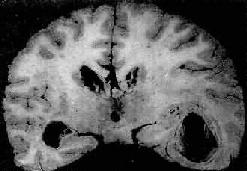

脑脓肿的发展规律和形态与全身其它器官的脓肿相似。急性脓肿发展迅速,境界不清,无包膜形成,可向四周扩大,甚至破入蛛网膜下腔或脑室,引起脑室积脓,可迅速致死。慢性脓肿边缘毛细血管和纤维母细胞(源于血管壁)增生明显,并伴有淋巴细胞和巨噬细胞浸润,形成炎性肉芽组织和纤维包膜,境界清楚。脓肿周围脑组织水肿明显,并伴有星形胶质细胞增生(图16-12)。

图16-12 慢性脑脓肿

右侧颞叶的脑脓肿与侧脑室相通